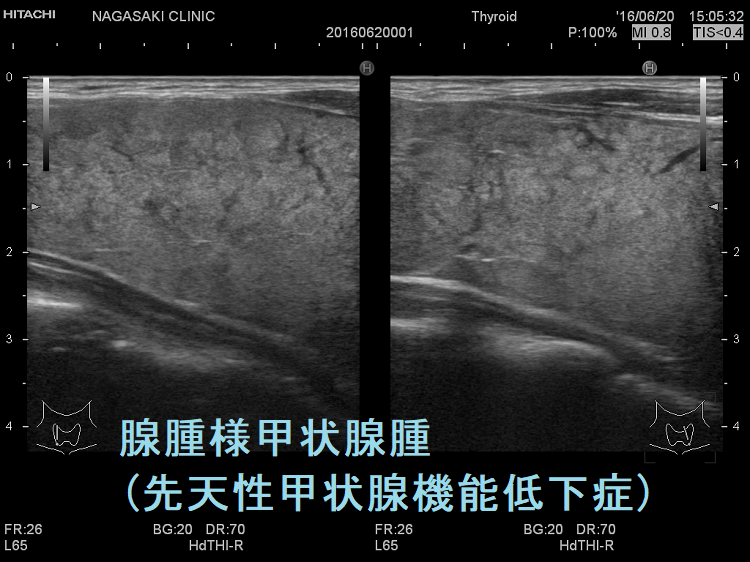

伊藤病院の報告では、

- 甲状腺腫を有する先天性甲状腺機能低下症患者の71%に、10mm以上の甲状腺結節が認められる

- 甲状腺腫あるいは甲状腺結節を有する先天性甲状腺機能低下症患者は、全例が遺伝性甲状腺ホルモン合成障害

とされます[ Thyroid. 2023 May;33(5):556-565.]。

遺伝性甲状腺ホルモン合成障害で、サイログロブリン異常症(サイログロブリン遺伝子異常症)以外は、血中サイログロブリンが上昇するにも関わらず、甲状腺自体の破壊性変化に乏しく、マシュマロ様の軟らかい腺腫様甲状腺腫の形態を取る事があります。

ケース⑦

遺伝性甲状腺ホルモン合成障害に橋本病(慢性甲状腺炎)を合併

他の甲状腺ホルモン合成障害と同じく、マシュマロ様の軟らかい腺腫様甲状腺腫の形態を取ります。しかし、サイログロブリン遺伝子異常症と異なり、癌の発生は稀です。

遺伝性甲状腺ホルモン合成障害の超音波(エコー)画像は色々なパターンがあります。

- 常染色体優性遺伝型;腺腫様甲状腺腫の形態になります。